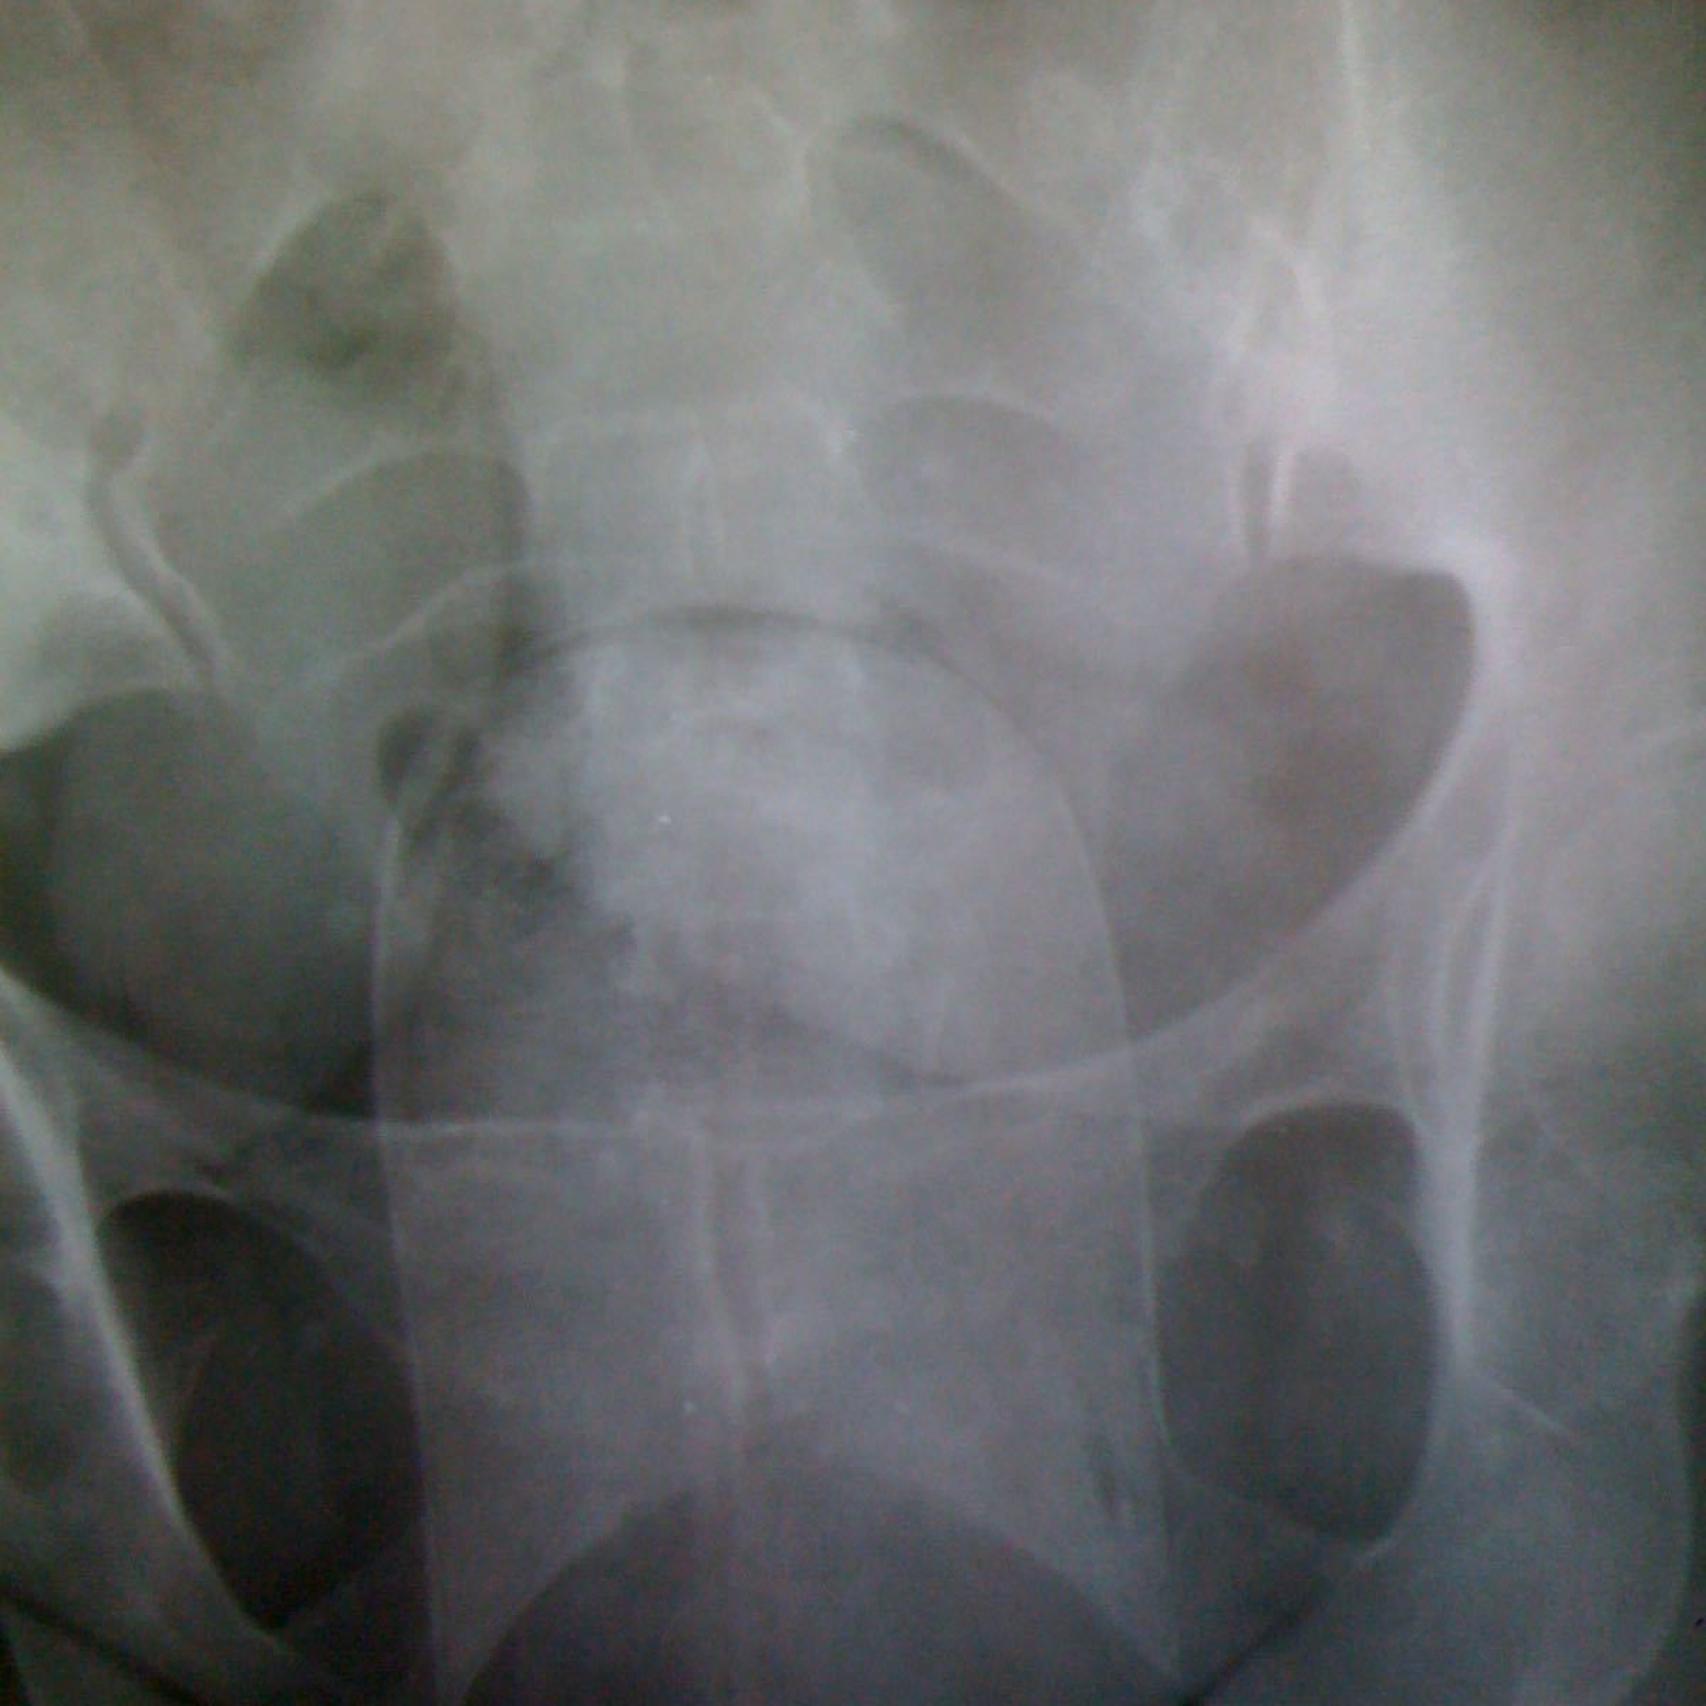

En la comisaría del aeropuerto de Barajas, once mujeres procedentes de Colombia son registradas por la Policía Nacional. Han llegado en un vuelo de Avianca y en dos de Iberia, procedentes todos del aeropuerto José María Córdova (Medellín). Los agentes sospechan que esconden droga. Tras negar los cargos, son examinadas en una sala de rayos X. Las radiografías revelan la presencia de cuerpos extraños en sus respectivos úteros. La más joven de todas, una chica de 22 años, pide entrar en los servicios y ahí se extrae un 'pepino' de la vagina. O lo que es lo mismo: un paquete de cocaína de casi 600 gramos de peso. Las dimensiones del bulto son tan grandes que la mujer acaba sangrando.

Las once colombianas, de entre 22 y 47 años, ya están en prisión. Todas ellas proceden de la zona baja de Medellín. Fueron interceptadas la semana pasada por la policía del aeropuerto de Madrid, en la que ha sido la operación contra el narcotráfico más numerosa de cuantas se han practicado en Barajas en los últimos 6 años. La policía las denomina 'pepineras', porque su método de transporte de droga consiste en introducirse en la vagina un paquete de cocaína de medio kilo. En la jerga policial, este bulto es conocido como 'pepino'.

Cuatro de los paquetes con droga que las mujeres transportaban en sus vaginas. Los test se vuelven azules cuando la sustancia es cocaína.